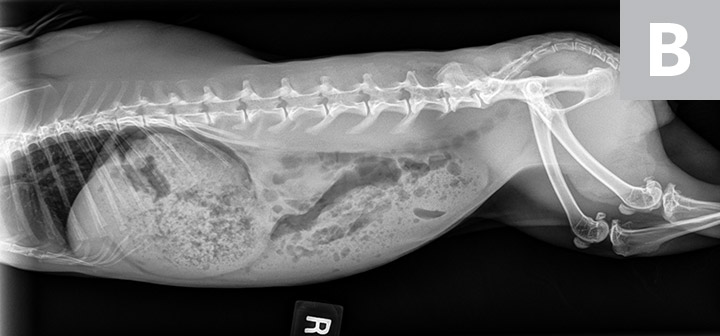

Victor was sedated with midazolam (0.5 mg/kg IM) to reduce stress during IV catheter placement and diagnostic testing. Abdominal radiographs (Figure 2) showed heterogeneous material in the stomach, which was inappropriately large for an anorexic rabbit; no obstructive pattern was seen.

FIGURE 2A

Abdominal and partial thoracic radiograph, left lateral view (A); abdominal and partial thoracic radiograph, right lateral view (B); and abdominal and thoracic radiograph, ventrodorsal view (C) showing heterogeneous material in the stomach but no obstructive pattern